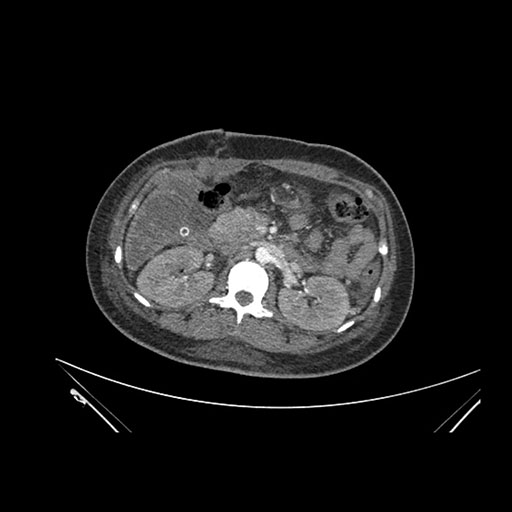

Imaging Analysis

Look through the patient's CT scan to identify any areas of concern for the necessary procedure.

Axial Venous